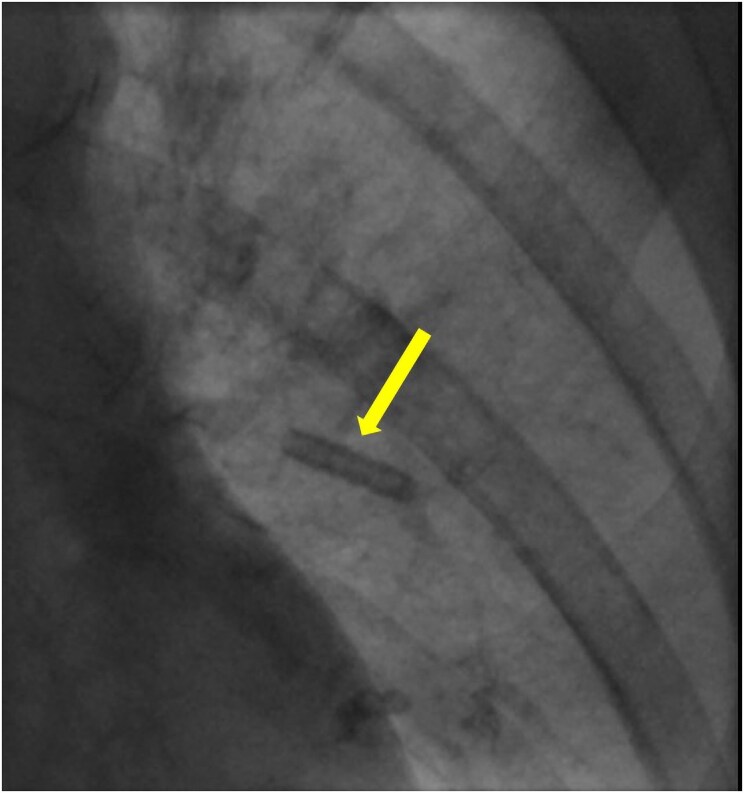

Case summary: An 82-year-old lady underwent PPM implantation for symptomatic 9-second sinus pause. During procedure, the anchoring sleeve from the atrial lead embolized through cephalic vein to the left superior lingular artery. The patient remained haemodynamically stable and multimodality imaging demonstrated only a small affected area of lung with patent pulmonary blood flow distal to the sleeve. Therefore, the patient was managed with anticoagulation alone and has remained well at 26-month follow-up.